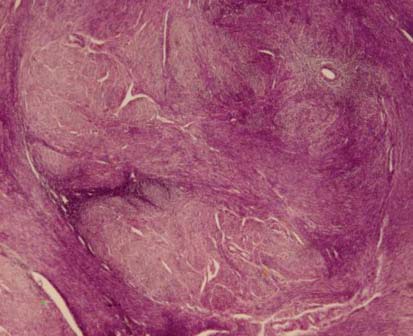

Лейомиоматозная пролиферация обнаруживалась также в цитогенной строме очагов Ам, в непосредственной топографической связи с сосудами микроциркуляторного русла (рис. 2). В ряде случаев на основе гладкомышечных пролифератов вокруг очагов Ам формировались множественные микрои макроскопически видимые лейомиомы (рис. 3).

Рис. 3. ПЛГ с формированием микромиом. Окраска – гематоксилин-эозин, ув. х200

В связи с этим было выделено два варианта ПЛГ: 1 – диффузная ПЛГ без формирования микромиом (97,8%); 2 – ПЛГ с формированием микрои/или макроскопически видимых миом (62,6%). Выраженность ПЛГ зависела от степени распространения ЭГ в толще миометрия. Так, ПЛГ в 1-й группе достоверно чаще была выражена слабо, а во 2-й группе – умеренно или резко выражена (табл. 1).